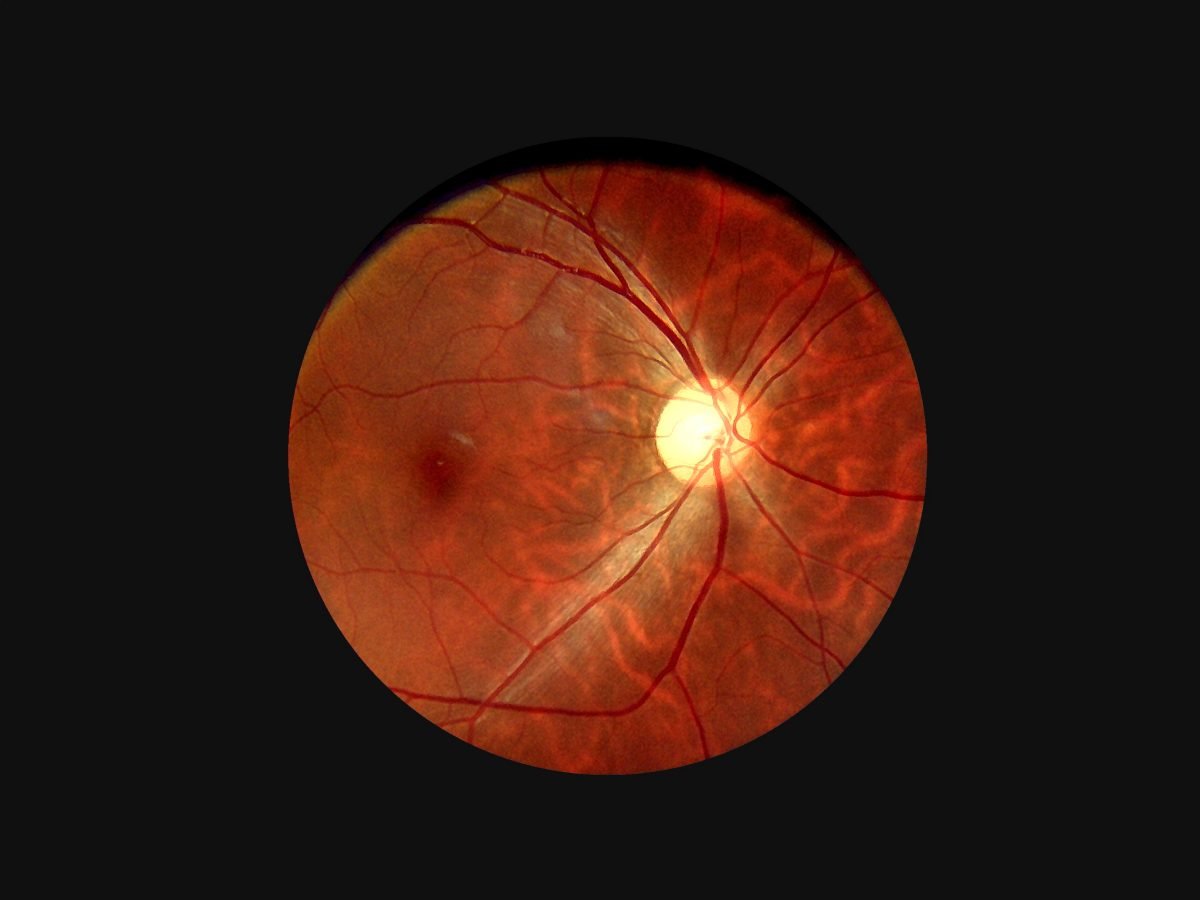

- Provide high definition clinical image

- Portable and hand held application in disease screen

- Multi functional diagnosis in ophthalmology , ENT . Dermatology and general practice.

Image Gallery

Through the scope